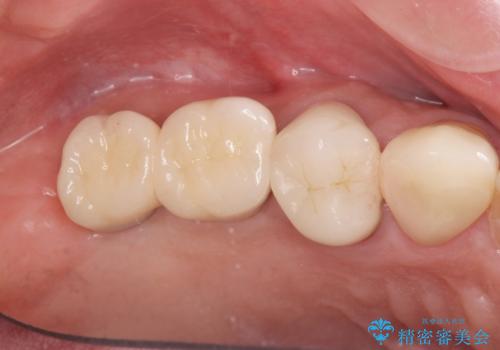

天然の歯のようにしっかりと噛むことができるようになり、またしっかりと食事を楽しんでいただけるようになりました。